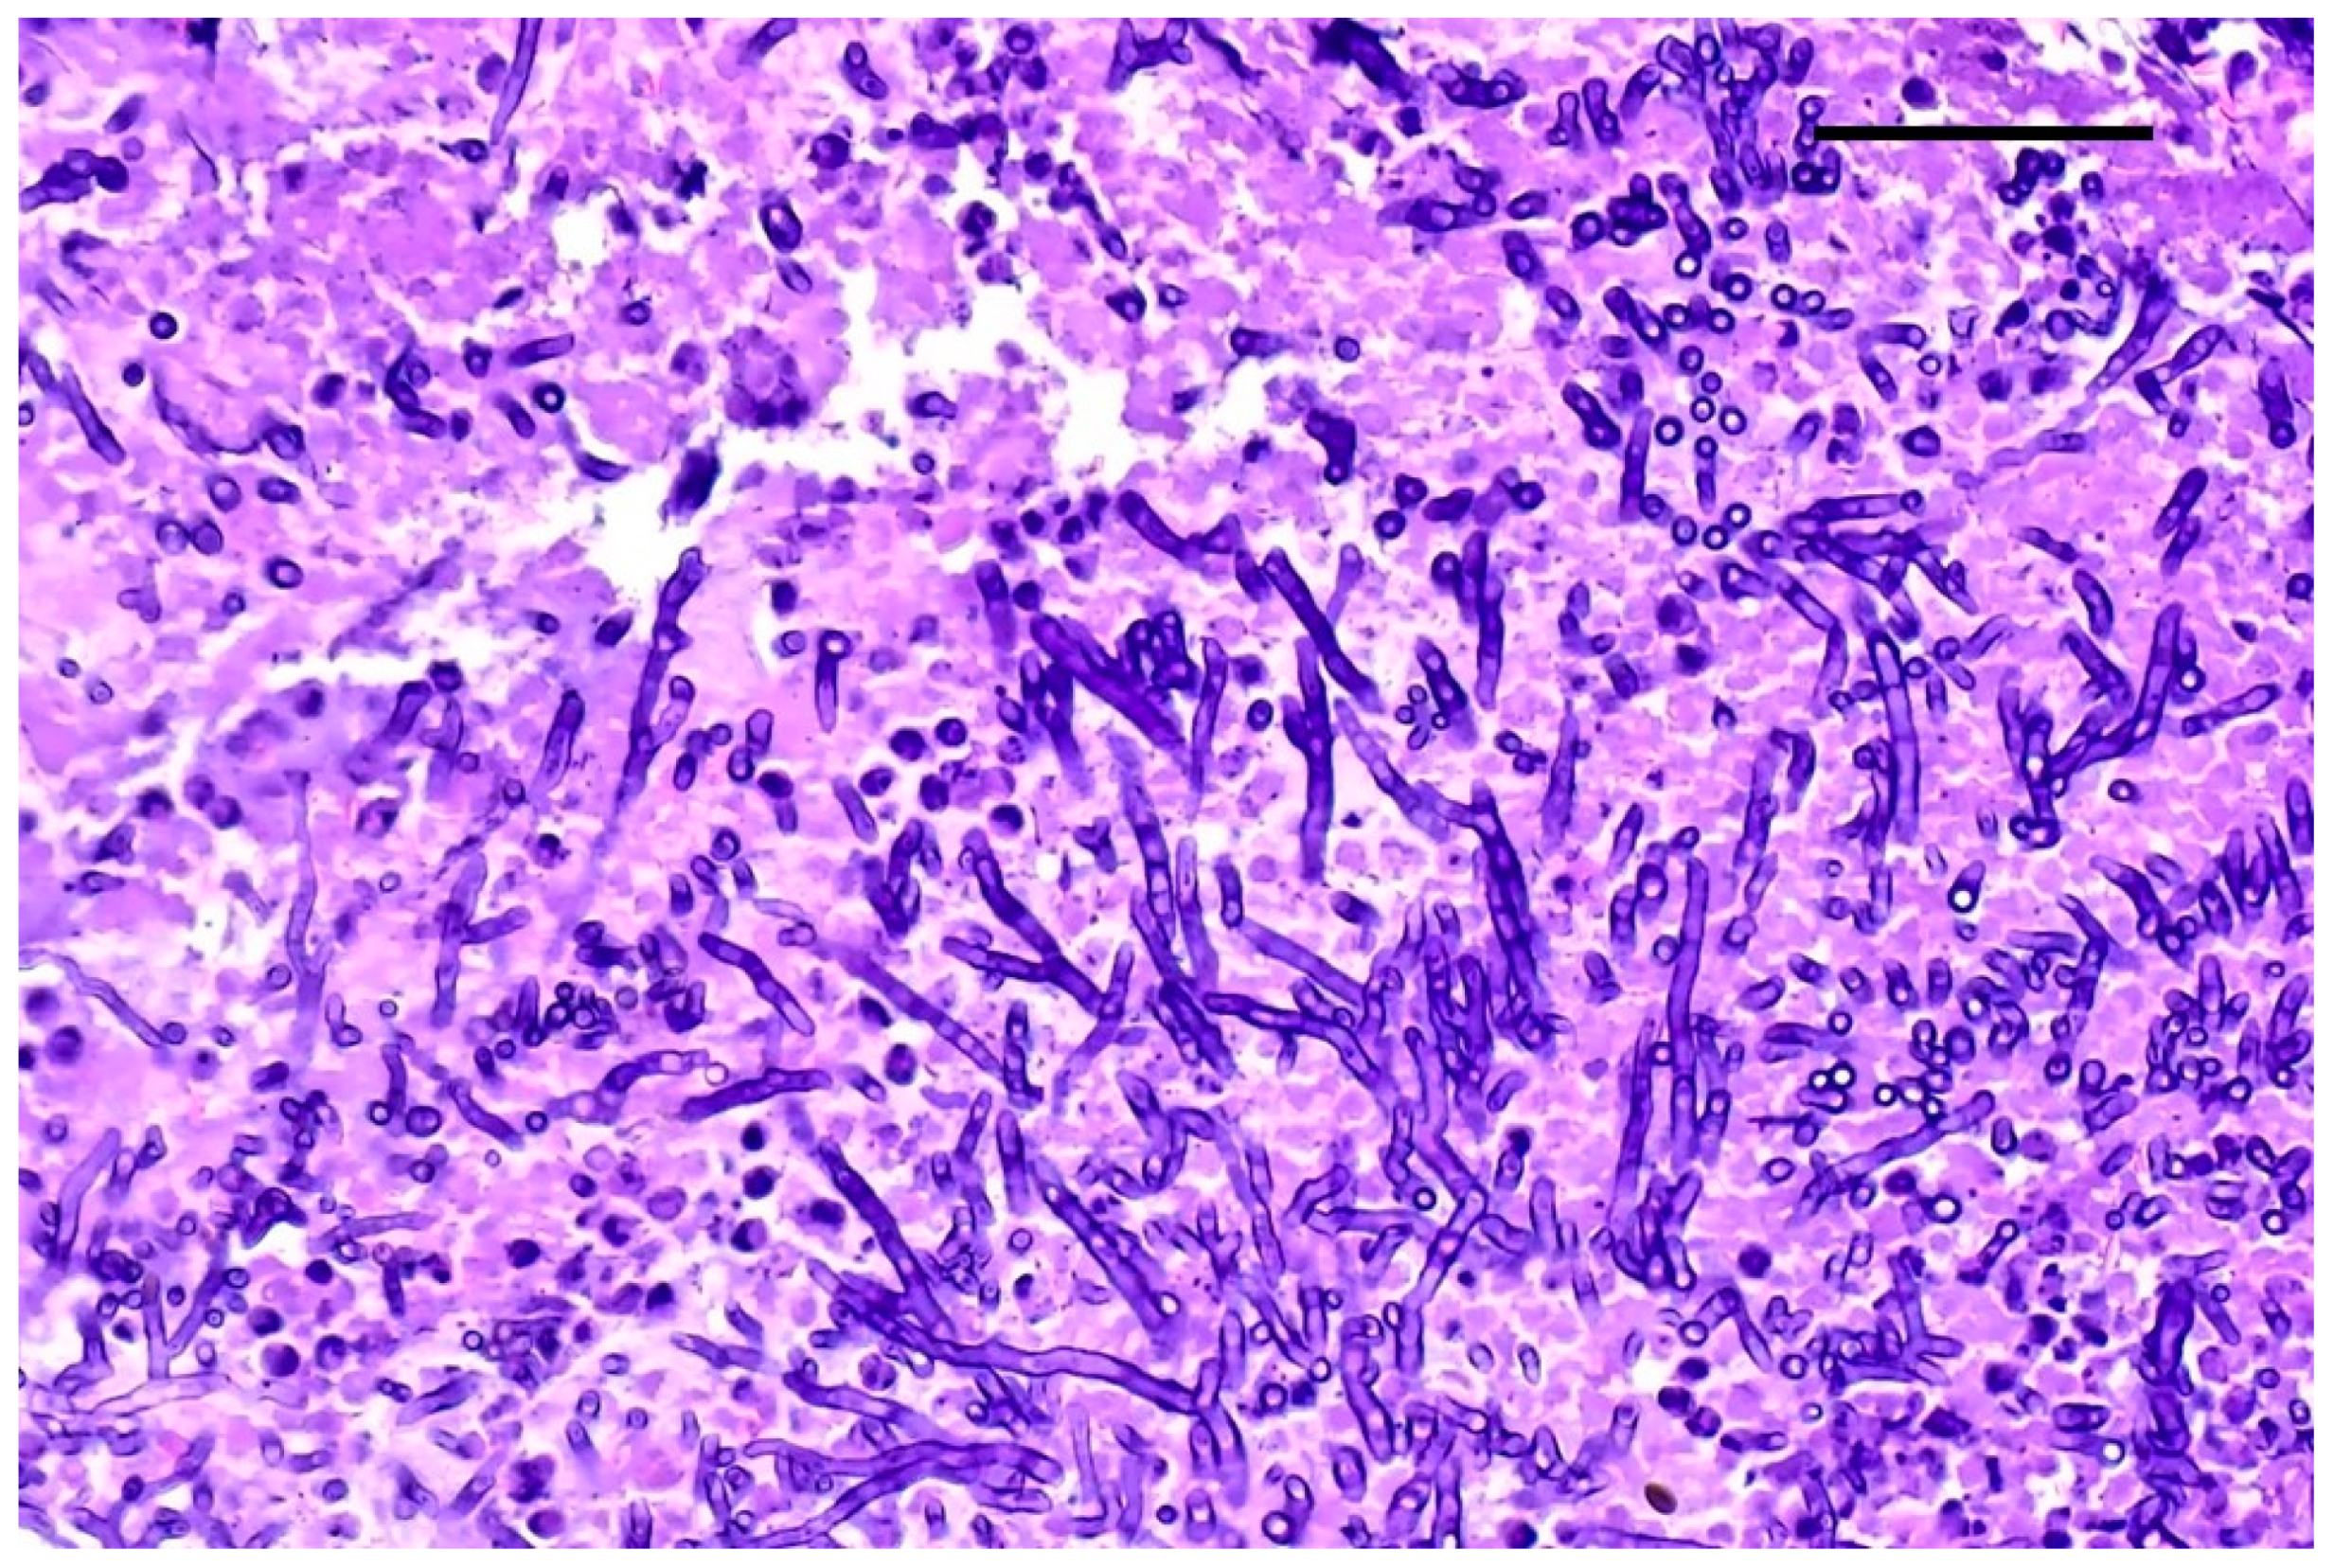

2.5. Histopathological Examination